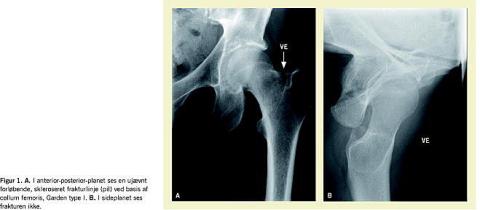

Ved radiologisk undersøgelse sås der i anterior-posterior-planet en ujævnt forløbende, skleroseret frakturlinje ved basis af collum femoris, Garden type I. I sideplanet sås frakturen ikke (Figur 1 ).